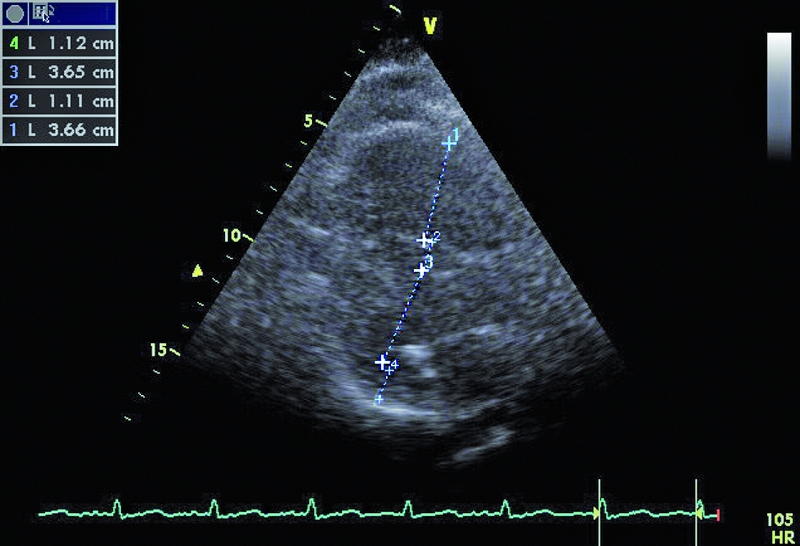

Powodem hospitalizacji 74-letniej kobiety był wielogodzinny ból w klatce piersiowej z towarzyszącą dusznością i niskim ciśnieniem tętniczym (90/60 mm Hg). W dniu hospitalizacji wystąpiło także krótkotrwałe omdlenie. W EKG zwracały uwagę cechy przebytego zawału serca ściany dolnej oraz brak progresji załamka R w odprowadzeniach V1-V4. Pacjentka od kilku lat chorowała na cukrzycę i nadciśnienie tętnicze. Po krótkotrwałym pobycie na oddziale szpitala rejonowego chorą przeniesiono do ośrodka referencyjnego. W wykonanej w trybie pilnym koronarografii uwidoczniono nieistotne zmiany miażdżycowe w naczyniach wieńcowych – maksymalnie do 40%. Wywiad, dziesięciokrotnie podwyższone stężenie d-dimeru i troponiny oraz powiększenie jamy prawej komory w badaniu echokardiograficznym stanowiły podstawę do poszukiwania zatorowości płucnej. Wykonane badanie TK klatki piersiowej pozwoliło uwidocznić skrzeplinę obejmującą pień oraz gałęzie płucne do poziomu tętnic segmentalnych. Ze względu na brak poprawy klinicznej w trakcie podawania heparyny zastosowano leczenie fibrynolityczne (alteplaza). Z powodu gorączki zastosowano także antybiotyk. W USG jamy brzusznej nie stwierdzono procesu nowotworowego, a badanie układu żylnego kończyn dolnych uwidoczniło skrzeplinę w żyle podkolanowej. Po kilku dniach od podania leku fibrynolitycznego obserwowano stopniowe ustępowanie duszności, stabilizację ciśnienia tętniczego, zmniejszenie parametrów zapalnych i stężenia d-dimeru. Rejestrowano także wzrost ciśnienia parcjalnego tlenu we krwi obwodowej. Dziesięć dni później wykonano kontrolne badanie echokardiograficzne (ryciny).

Dowodem klinicznym masywnej zatorowości płucnej był u chorej epizod omdlenia, utrzymująca się duszność, niskie ciśnienie tętnicze. Wiodącą rolę w rozpoznaniu choroby pełni tomografia komputerowa. Badanie echokardiograficzne uznawane jest za uzupełniające. Powiększenie jamy prawej komory stwierdzane w dniu hospitalizacji mówiło o możliwości istotnej dysfunkcji łożyska płucnego. Masywna zatorowość jest wskazaniem do włączenia leczenia fibrynolitycznego, zmniejszającego śmiertelność i zapobiegającego nawrotom choroby. Stan kliniczny pacjentki w wyniku zastosowanej alteplazy poprawił się. Rejestrowano zmniejszenie stężenia d-dimeru i troponiny. Czy jednak sytuacja chorej nie budzi już niepokoju? Mimo ograniczonej jakości przedstawionych rycin można dostrzec, że jama prawej komory jest przeciążona (ryc. 1, 2), a ciśnienie w łożysku tętnic płucnych szacowane z czasu akceleracji wypływu (66 ms!) jest podwyższone (ryc. 3). Im większa jest obstrukcja łożyska płucnego, tym więcej cech dysfunkcji prawej komory stwierdza się w badaniu ultradźwiękowym. Warunki obrazowania utrudniały odniesienie się do odcinkowej kurczliwości ściany wolnej i potwierdzenie lub wykluczenie objawu McConnella, czyli dysfunkcji segmentu środkowego. Ze względu na trudność w wizualizacji wsierdzia nie można było także ocenić zmiany pola powierzchni prawej komory (RV FAC). Mimo zachowanej funkcji kurczliwej prawej komory mierzonej wartością przemieszczenia pierścienia trójdzielnego (ryc. 4) uważny czytelnik z pewnością dostrzeże tkwiącą w prawej tętnicy płucnej skrzeplinę (ryc. 5, 6). Rzadko udaje się bezpośrednio uwidocznić skrzeplinę w łożysku tętnic płucnych. Kontrolne badanie TK klatki piersiowej potwierdziło obecność tzw. zatoru jeźdźca w pniu płucnym ze skrzeplinami w gałęzi prawej i gałęziach segmentalnych do płata dolnego prawego płuca. Obserwowano jedynie częściową regresję skrzeplin z tętnic płatowych i segmentalnych. Mamy więc do czynienia z nieskutecznością leczenia fibrynolitycznego (no clot resolution). Dobry stan kliniczny chorej nie wskazywał na potrzebę zastosowania leczenia chirurgicznego i embolektomii. Nie podjęto także decyzji o powtórnym leczeniu fibrynolitycznym z użyciem innego środka. Postanowiono kontynuować leczenie przeciwkrzepliwe i przeprowadzić po kilku tygodniach ponowną ocenę stanu klinicznego pacjentki i stanu łożyska tętnic płucnych. Wobec wieku chorej i licznych obciążeń internistycznych interesującą opcją leczenia (ale niestosowaną w tutejszym ośrodku) byłaby trombektomia za pomocą cewnika z miejscowym podaniem leczenia fibrynolitycznego.